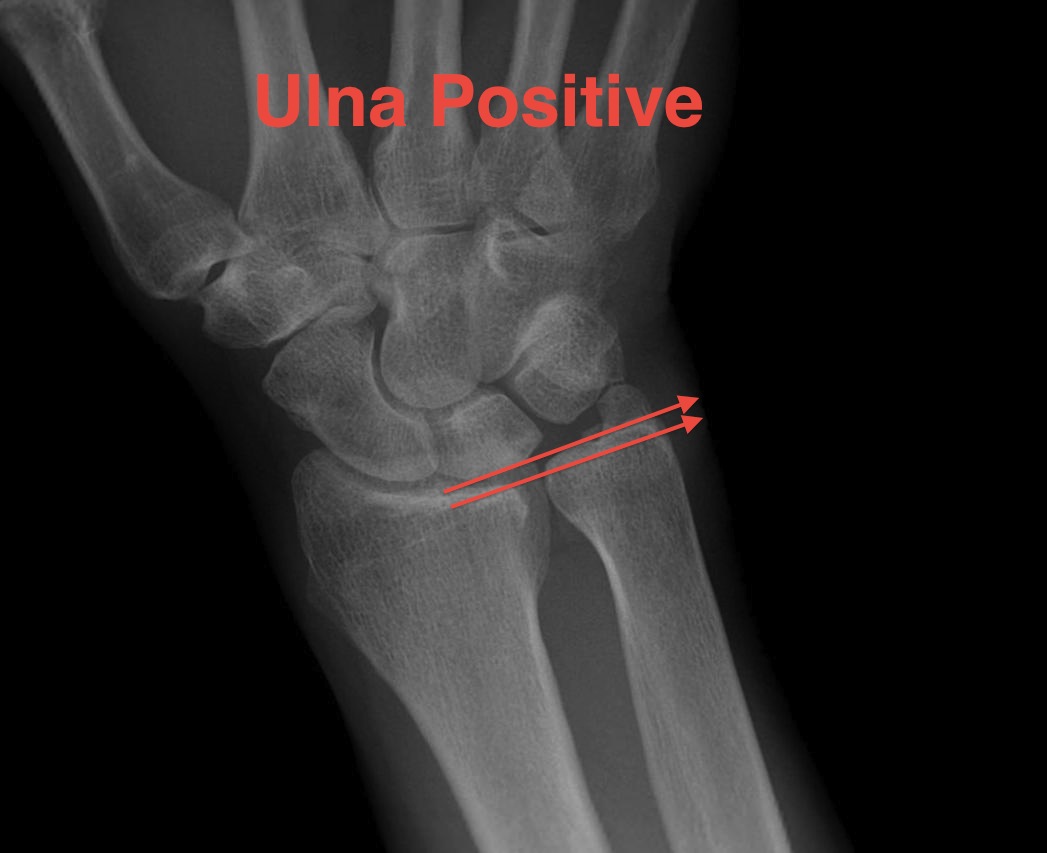

Ulna variance

Supination and pronation alter variance

- varies up to 3 mm with wrist position

- pronation increases ulnar variance

- supination decreases variance

90 / 90 view

- zero rotation view

- neutral supination / pronation

- PA film with wrist in neutral

- elbow 90° / shoulder abducted 90°

Line from lunate fossa and ulna head

- wide variation in population

- mean ulna variance is 1 mm (range 2 - 4)

Ulna neutral

Ulna positive

Ulna negative